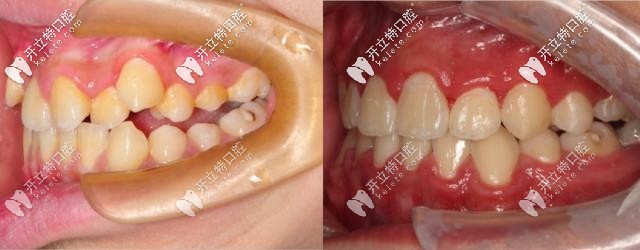

術(shù)前檢查:骨性地包天+牙列擁擠+咬合不對(duì)稱。

矯正方案:拔除A5B5和埋伏牙,選用進(jìn)口金屬自鎖牙。

矯正周期:兩年。

拔完牙后需要等待牙槽骨恢復(fù),中間過(guò)了約2周時(shí)間到院進(jìn)行帶牙套,然后是一個(gè)月一次的復(fù)診,一起來(lái)看看兩年后的小哥哥牙齒情況吧!

可以看到,本來(lái)?yè)頂D的牙齒已經(jīng)排列整齊,咬合也已經(jīng)調(diào)整對(duì)稱,誰(shuí)說(shuō)地包天不能矯正呢!這個(gè)效果是不是很贊呢!